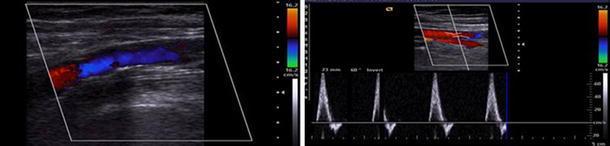

A total of 1,000 knees of 692 patients who underwent primary TKA due to osteoarthritis were preoperatively evaluated by experienced musculoskeletal radiologists using Doppler ultrasonography of the lower extremity vessels. The mean age of the patients was 74.1 years (range 65-81). Risk factors for development of peripheral vascular disease were investigated.

Abnormal findings were identified in 38 knees of 32 patients (4.6 %); atherosclerotic changes in 31 knees of 25 patients (3.6 %), deep vein thrombosis (DVT) in two knees, and anomalous vessels in five knees. Three out of 31 knees with atherosclerotic changes showed severe luminal stenosis. Two knees were moderate and 26 knees showed mild changes according to our institutional criteria. Multivariate logistic regression analysis showed that age and diabetes mellitus were positively associated with vascular pathology.